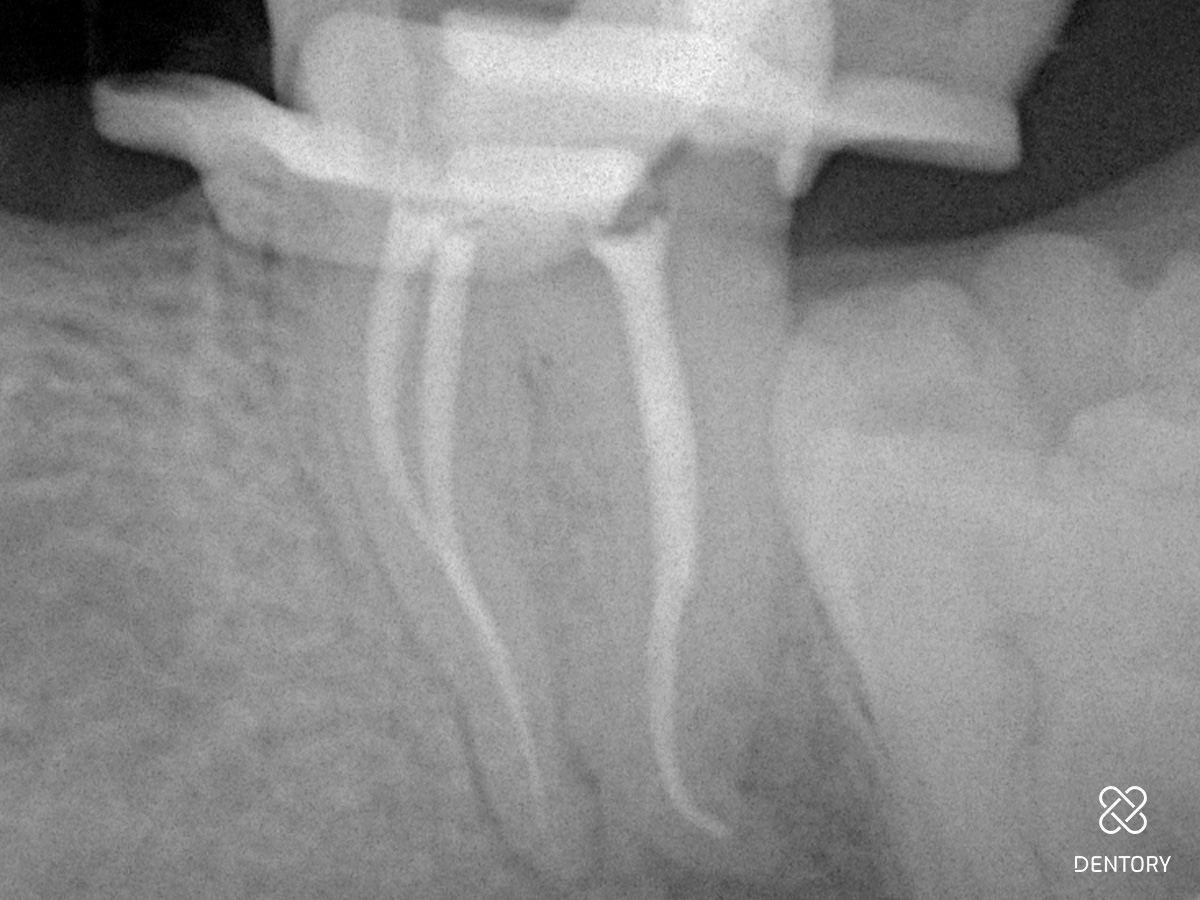

Abbildung 2

Röntgen-Messaufnahme: Aufgrund der Kanalkrümmung erfolgte die Messaufnahme bereits nach der Erstellung eines Gleitpfades bis ISO 10. Der mb und ml Kanal verfügen jeweils über ein separates Foramen.